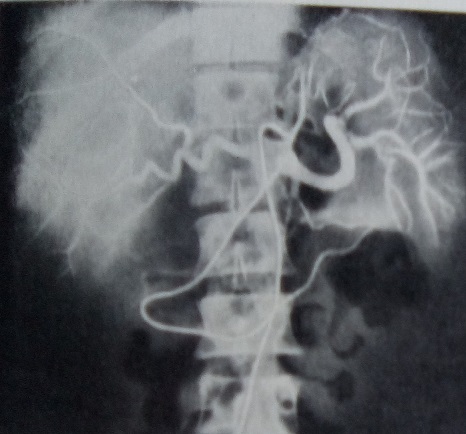

Archivo:Albeococosis.jpg